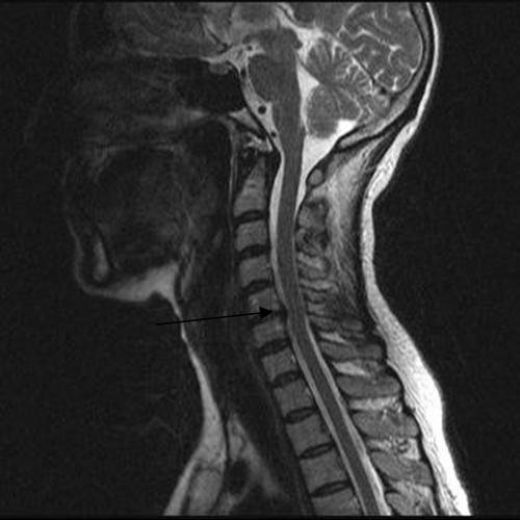

Boyun fıtığı, tıbbi olarak servikal disk hernisi olarak adlandırılan bir durumdur ve omurganın boyun bölgesinde yer alan disklerin kayması veya yırtılması sonucu ortaya çıkar. Bu durum, sinir köklerine veya omuriliğe baskı yaparak çeşitli semptomlara yol açabilir. Boyun fıtığı ameliyatı, konservatif tedavi yöntemlerinin başarısız olduğu durumlarda önerilen cerrahi bir müdahaledir. Ancak, bu tür bir ameliyatın riskleri ve sonrası hakkında bilgi sahibi olmak önemlidir.